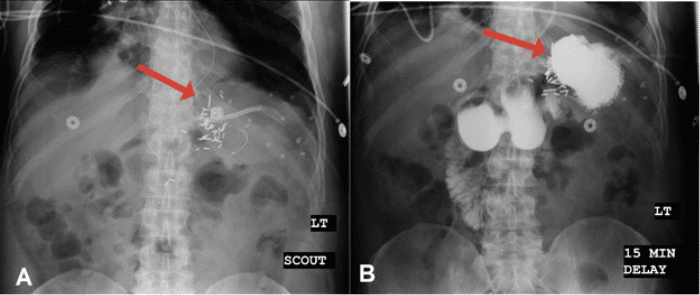

The patient tolerated the procedure well. He remained intubated postoperatively and was transferred to the intensive care unit for recovery. On postoperative day 1, the patient was successfully extubated. An upper GI X ray on postoperative day 3 confirmed an intact repair (Figure 4).

Figure 4. Upper GI X Ray Demonstrating Stomach Projecting Under Diaphragm A) Before and B) After Contrast. Published with Permission